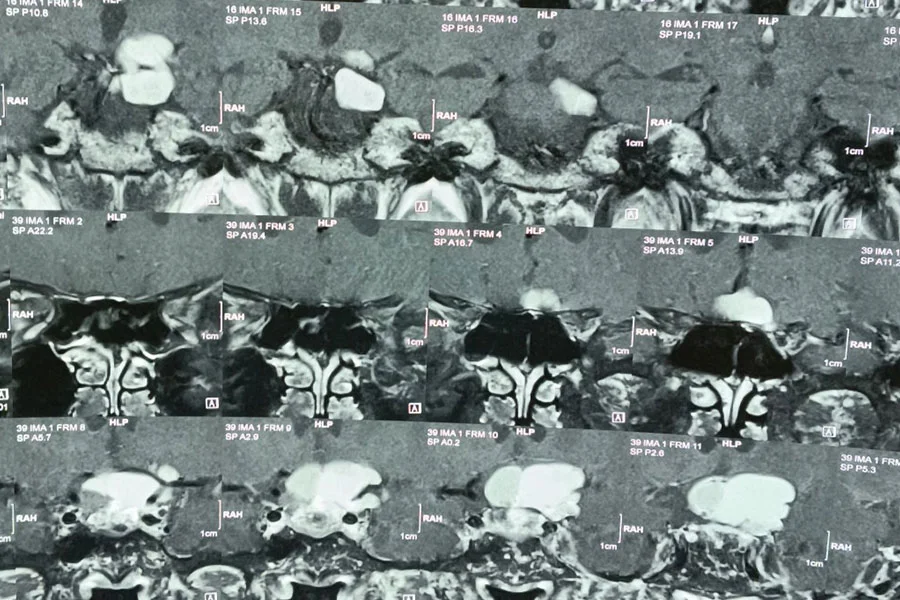

Craniopharyngioma surgery involves the removal of a benign but complex tumor located near the pituitary gland and optic nerves. Due to its proximity to critical structures, treatment requires a highly specialized, multidisciplinary approach involving neurosurgeons and ENT skull base surgeons. Surgery is commonly performed using minimally invasive endoscopic endonasal techniques, accessing the tumor through the nasal passages, or via traditional craniotomy in selected cases.

The goal is maximal safe tumor removal while preserving vision, hormonal function, and neurological status. Postoperative care may include hormone replacement and regular imaging follow-up. These surgeries are complex but can significantly improve symptoms and quality of life.